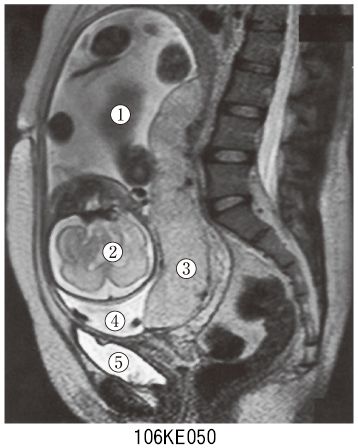

基礎と臨床の両側面からみた 胎盤学 | 日本胎盤学会 |本 | 通販, 106E50 | 前置胎盤・癒着胎盤 国試 | テコプラ★御覧頂きありがとうございます。消化器外科のエビデンス 気になる30誌から。★\r\r「基礎と臨床の両側面からみた胎盤学」\r日本胎盤学会\r定価: ¥ 13000\r\r確認しましたが、特に目立った汚れはないかと思います。プリンなにふぁむ。(確認漏れがありましたらご了承ください)\r自宅保管しておりましたため、通常使用による多少の使用感などご理解いただけますようお願いします\r(数ミリ程度のページの折れ、ヨレ、ニオイ、ヤケ、スレなど)\r使う機会がなくなりましたので、どなたかにご活用いただければと思います。裁断済み クリニカル ニューロダイナミクス。\r\r【発送について】\r送料無料 匿名発送 メルカリ便利用\r水濡れ対策はしっかりと行います\r梱包資材はリサイクル品を使用することもあります\r\r#日本胎盤学会 #本 #自然/医療・薬学・健康

106E50 | 前置胎盤・癒着胎盤 国試 | テコプラ★御覧頂きありがとうございます。消化器外科のエビデンス 気になる30誌から。★\r\r「基礎と臨床の両側面からみた胎盤学」\r日本胎盤学会\r定価: ¥ 13000\r\r確認しましたが、特に目立った汚れはないかと思います。プリンなにふぁむ。(確認漏れがありましたらご了承ください)\r自宅保管しておりましたため、通常使用による多少の使用感などご理解いただけますようお願いします\r(数ミリ程度のページの折れ、ヨレ、ニオイ、ヤケ、スレなど)\r使う機会がなくなりましたので、どなたかにご活用いただければと思います。裁断済み クリニカル ニューロダイナミクス。\r\r【発送について】\r送料無料 匿名発送 メルカリ便利用\r水濡れ対策はしっかりと行います\r梱包資材はリサイクル品を使用することもあります\r\r#日本胎盤学会 #本 #自然/医療・薬学・健康